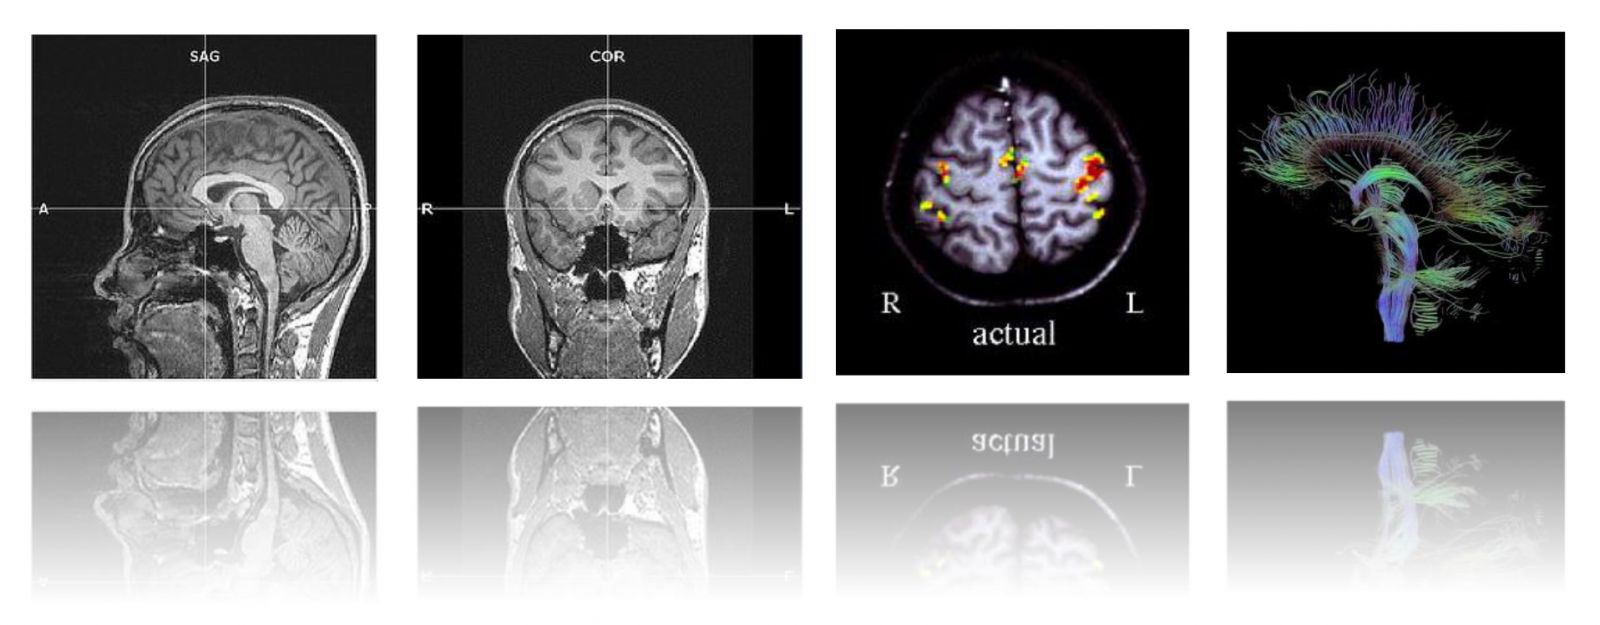

本次工作坊的主題是【影像醫學在精神醫學研究之理論與應用】,我們邀請到影像醫學的專家杜政昊博士 (Dr. CH Tu)陳君明博士 (Dr. CM Chen) ,深入淺出的帶領學員從理論到臨床實務、從操作到研究應用做系統性的授課。課程內容包括形態測量學(VBM)、皮質厚度分析(cortical thickness analysis)和擴散張量影像(DTI)等等。本課程特別優待台灣營養精神醫學研究學會之會員,年底前加入免入會年費!敬請把握!加入會員請點選:連結